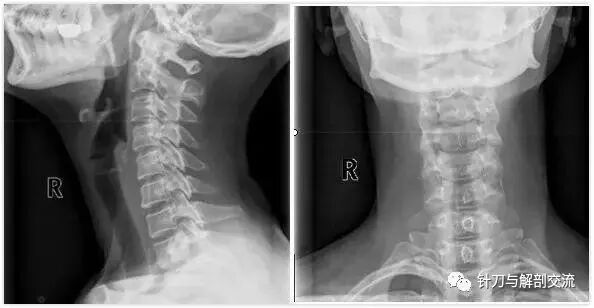

颈椎X线上可以看到:生理曲度变直、颈椎序列不齐、颈椎失稳、椎间隙变窄,椎体前缘增生,骨桥形成。

3、颈椎X线检查:常规拍摄颈椎正、侧、开口位X线 片,必要时加照颈椎左、右斜位及过伸、过屈位片有上述表现者;